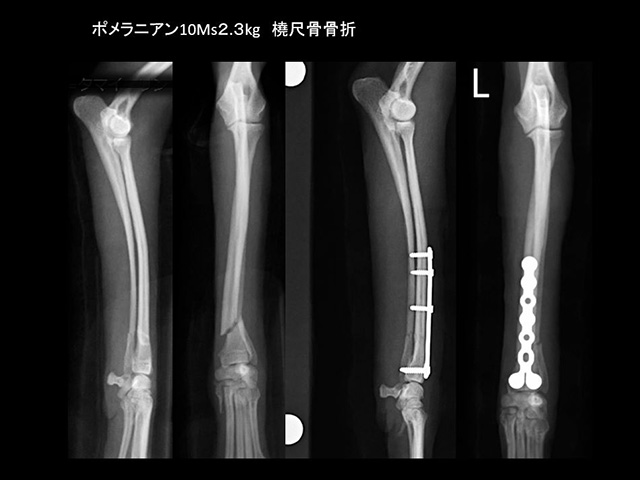

骨折Bone fracture

骨折症例の多くは、整復固定治療直後の運動機能回復と疼痛消失により、普段の活発さを取り戻します。従って、骨癒合までの間、活発さに耐えて初期固定を維持できる安定した固定法が求められます。